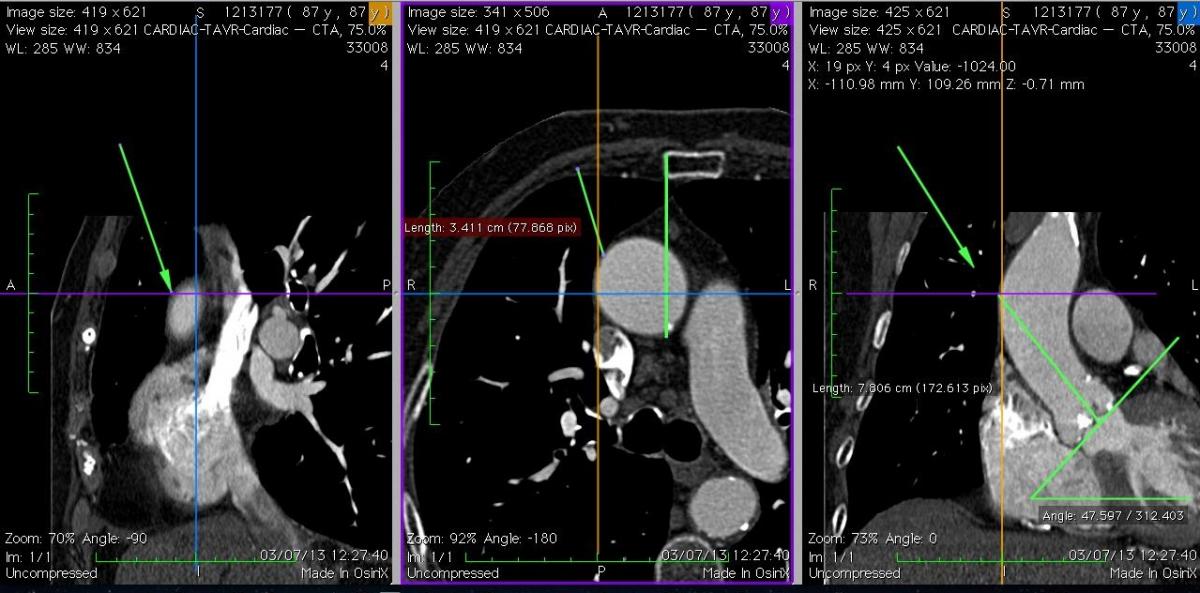

Fig. 6A: Case 2. In comparison to Case 1, the ascending aorta is more horizontal, and right-sided relative to the sternum. It was possible in this case to find a suitable puncture site at about 8 cm from the aortic annulus.

Fig. 6B: Case 2. The 3D volume rendering images revealed the right-sided and horizontal anatomy of the ascending aorta; this suggested that the optimal incision was a right upper mini-thoracotomy approach through the 2nd intercostal space.